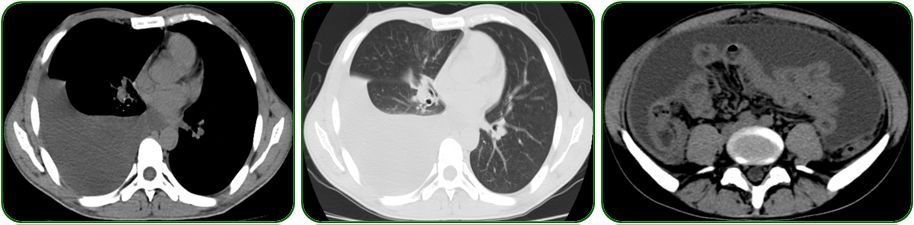

肺部及腹部CT提示右侧胸腔大量积液,右肺中下叶局限性膨胀不全、左肺上叶前段小结节影、纵隔稍肿大淋巴结、腹腔大量积液、盆腔少量积液、肝胆脾、胰腺及双肾CT平扫未见明显异常征象,如图5;

图5 胸部及腹部CT检查

基本该患者诊断结核感染,那到底是肺结核还是结核性腹膜炎,我们还需要进一步了解。肺部CT提示右侧胸腔大量积液,右肺中下叶局限性膨胀不全,右侧不能排除有无结核病灶,大量胸水可干扰观察,一般建议胸腔穿刺后复查肺部CT或胸片;如果不是肺结核,结核性腹膜炎会导致这样大量胸水吗?答案是肯定的,结核性腹膜炎导致腹腔大量积液很好理解,但腹腔大量腹腔积液也可以导致胸水。

查阅文献发现有以下几点原因:1)膈裂孔单向活瓣,腹水被胸腔负压抽吸;2)大量腹水将膈肌上台,导致胸腔内淋巴回流增加,淋巴管压力升高,导向胸腔淋巴管破裂;3)胸腔受压导致胸腔内脏血流的奇静脉半奇静脉压力高,因此极易产生胸腔积液,而且右侧胸水多见。

本例患者结核菌感染可以导致体内高代谢,腹水导致肠道蠕动能力下降,食欲较差,因此容易出现低蛋白血症,该患者生化全套提示白蛋白较低,低蛋白血症也会加重胸腔、腹腔积液。患者出院后就诊结核专科门诊,予正规抗结核治疗,同时辅以利尿、纠正低蛋白血症及加强营养支持治疗,2个月后腹水消失,定期门诊复查腹水未再复发。